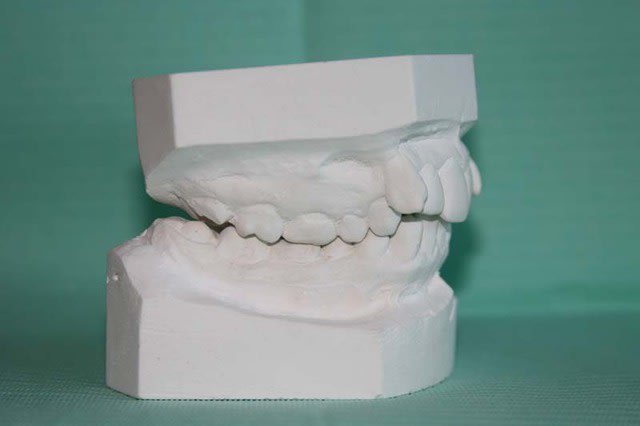

MOULAGES

Moulage 3 kvumyd - Eugenol

Moulage 1 vlrapq - Eugenol

Moulage 2 dllhb9 - Eugenol

Moulage 4 etnevt - Eugenol